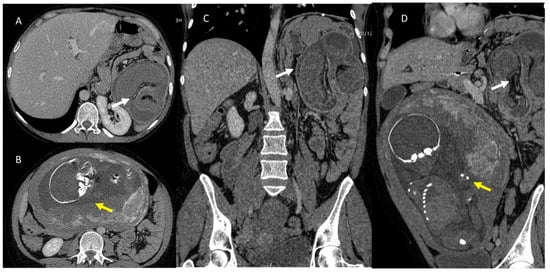

4. Clinical Setting: Abdominal Pain

6. Biliary Tract and Pancreatic Diseases

7. Ureterolithiasis